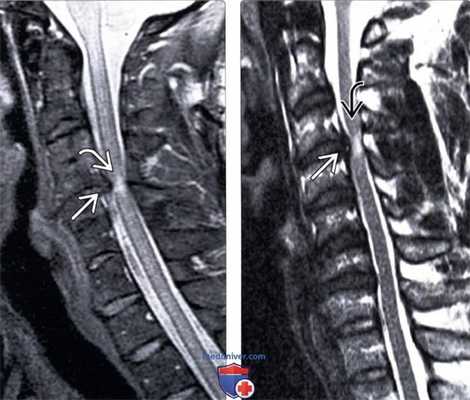

(Слева) На сагиттальном Т2-ВИ пациента с посттравматическим центральным спинномозговым синдром виден фокальный гиперинтенсивный сигнал спинного мозга на уровне С4-С5, свидетельствующий о контузии спинного мозга. Обратите внимание на признаки исходного стеноза спинномозгового канала за счет выраженных спондилофитов замы кательных пластинок позвонков на этом уровне.

(Справа) Т2-ВИ сагиттальная проекция: гиперинтенсивность сигнала спинного мозга на уровне С3-С4. В дополнение к врожденному стенозу спинномозгового канала у этого пациента имеет место протрузия диска СЗ-С4, ставшая причиной еще большего усугубления стеноза спинномозгового канала.

(Слева) Т2-ВИ, сагиттальная проекция: признаки многоуровневого дегенеративного поражения шейного отдела позвоночника. На уровнях С3-С4 и С4-С5 отмечается выраженный стеноз спинномозгового канала за счет протрузий межпозвонковых дисков, спондилофитов замыкательных пластинок тел позвонков и гипертрофии дорзальных связок. После травмы у данного пациента развилась клиника центрального спинномозгового синдрома, свидетельством чего является небольшой гиперинтенсивный очаг в зоне повреждения спинного мозга на уровне С4-С5.

(Справа) На сагиттальном STIR МР-И пациента с травмой шейного отдела позвоночника видны признаки врожденного стеноза спинномозгового канала и минимально выраженных дегенеративных изменений. На уровне цервикомедуллярного перехода и С4 отмечается патологическое усиление Т2-сигнала спинного мозга, свидетельствующее о его повреждении. Обратите внимание на гиперинтенсивность сигнала превертебральных мягких тканей (гиперэкстензионное повреждение).